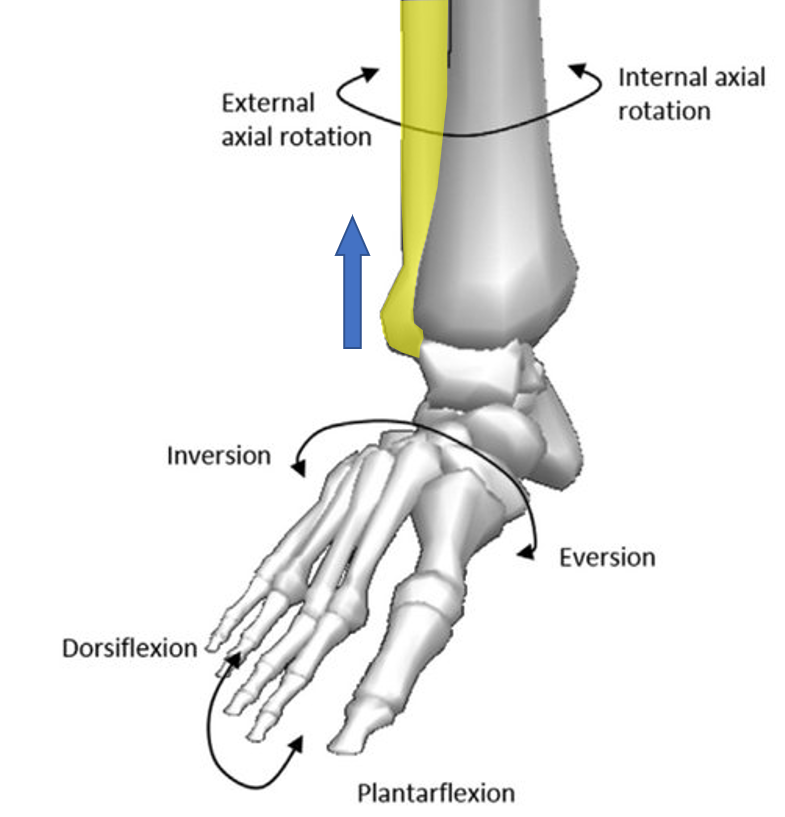

ANATOMY 11 – LEG/ANKLE JOINT at Nanyang Polytechnic – StudyBlue

Making Sense of the Ankle joint : Part 1 – Revision of Ankle Joint …

CrossFit | Bones of the Foot and Ankle